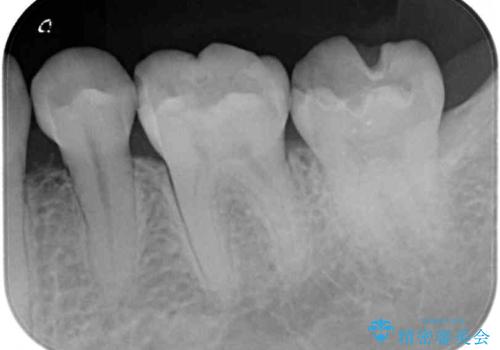

- 下の奥歯に虫歯ができてしまったとのことで来院された患者様です。

他にも気になる歯はありましたが、急を要する1歯のみをセラミックインレーにて修復治療を行うこととしました。

奥歯において、隣の歯と接触する部分に虫歯が及んでしまった場合、その場で充填を行う処置(コンポジットレジン修復)ですと、充填の縁に大きなギャップが生じてしまう可能性が高く、2次的な虫歯を引き起こすことになります。

また、処置した歯の後方にある歯は保険診療で使用するレジンインレーが装着されていますが、縁に虫歯が出来はじめていることが分かります。